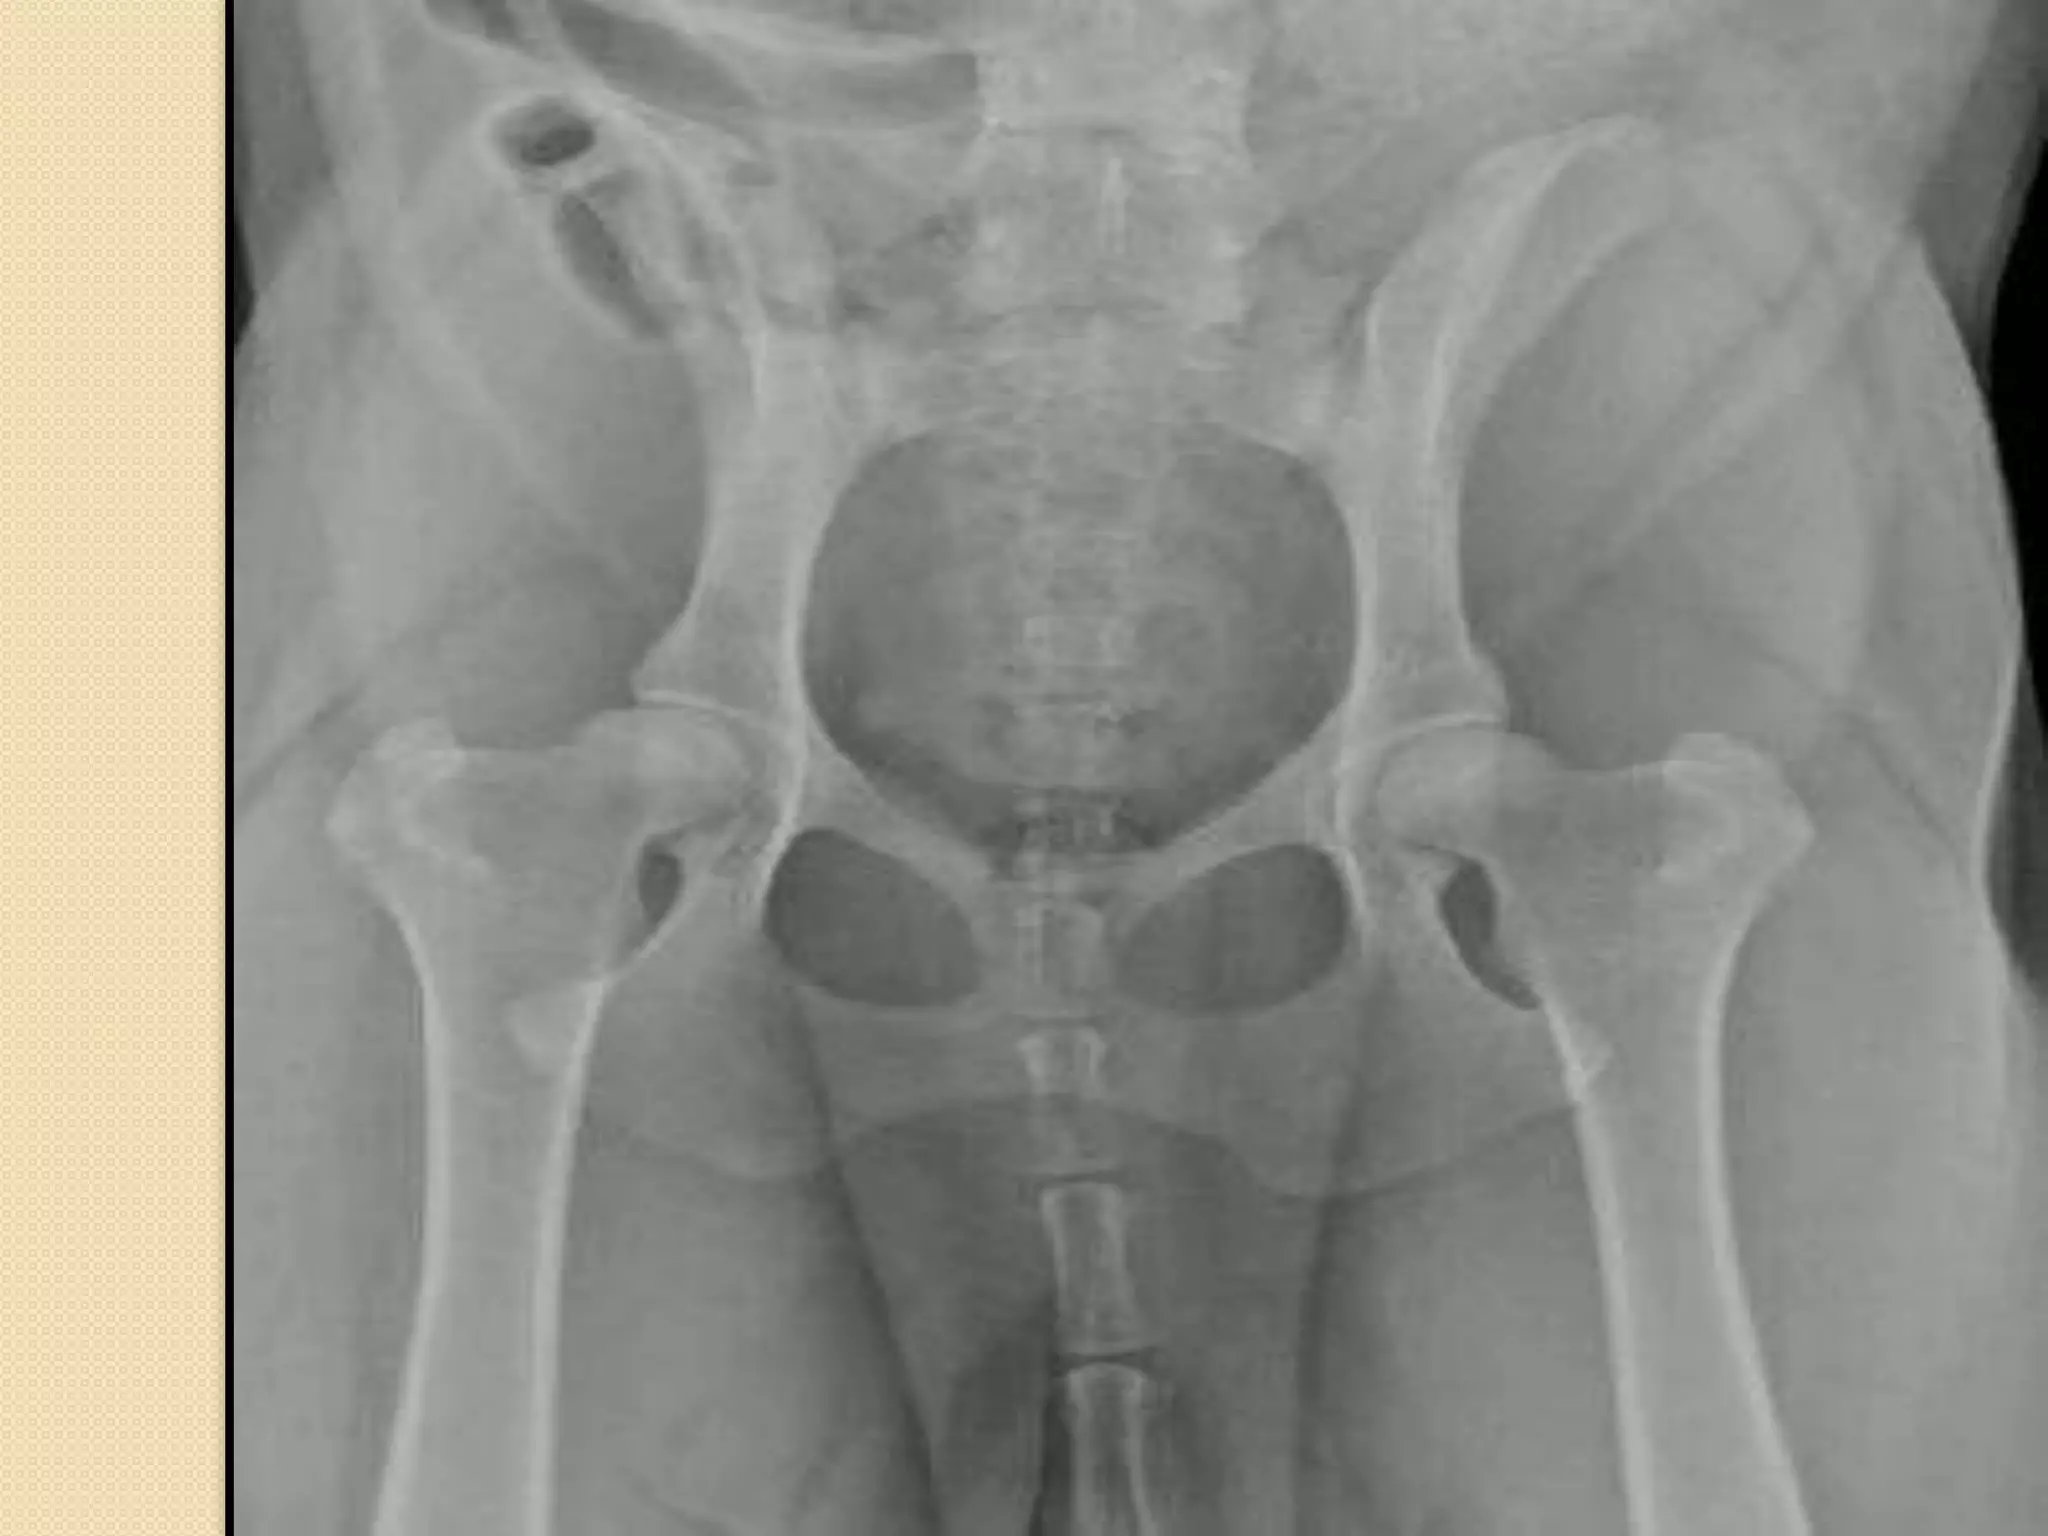

Os coxae :

It is the first bone in the hind limb which form the pelvis

The right and left bone fused with each other by the pelvic symphysis

It consist of 3 bones ilium- ischium and

pubis

The gluteal surface is concave ( spoon like)

Hip joint:

Hip joint is formed of the head of the femur

with the acetabulum of os coxae.